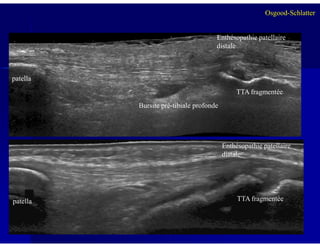

patella

Bursite pré-tibiale profonde

TTA fragmentée

Enthésopathie patellaire

distale

Osgood-Schlatter

3838